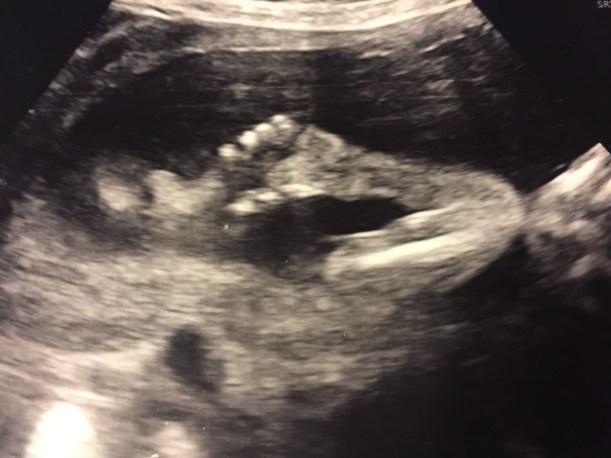

Käänne tapahtui raskausviikolla 20. Alkuraskaus oli sujunut tavanomaisesti. Menin rakenneultraan Kätilöopistolle suoraan työpalaverista, josta lähtiessäni huikkasin, että ”menemme kuulemaan lapsen sukupuolen.” Odotettu tieto jäi kuitenkin muiden uutisten varjoon.

”Täällä on molemmat kädet ja kymmenen sormea. Ja jalat ja kymmenen varvasta ja kaikki ihan normaalisti, mutta – – -”

Siihen sanaan elämämme pysähtyi. Sikiön niska ja kaula näyttivät normaalia paksummilta. Kätilö kutsui kollegansa tutkimaan ultraäänikuvaa, ja sitten lääkärin. Tässä vaiheessa varmaan jo itkin, ja puolisoni istui hiljaa vieressäni kädestäni pidellen. Saimme seuraavalle päivälle kiireellisen ajan Naistenklinikan Sikiötutkimusyksikköön.

Sikiön niskan turvotuksen syystä kuulimme lääkäreiltä sen sijaan monia arvioita. Lukuisten ultraäänitutkimusten, lapsivesitutkimuksen ja magneettikuvauksen jälkeen saimme melko varman diagnoosin: lapsella on lymfaattinen malformaatio eli imutie-epämuodostuma. Jaa mikä? Niinpä, tässä vaiheessa emme tienneet tästä erittäin harvinaisesta sairaudesta yhtään mitään.

Näillä mentiin ja jännitettiin synnytystä. Sikiötutkimusyksikössä kävimme usein. Sikiön kehitystä seurattiin ultraäänellä tiheimmillään joka toinen viikko. Synnytys aikataulutettiin joulun välipäiville kuukautta ennen laskettua aikaa. Viikkoa ennen synnytystä vauvan intuboinnista vastaava kirurgi kävi tervehtimässä meitä Naistenklinikalla käydessämme. Hänen sanoistaan syntyi taas uusi mantra, jonka varaan laskimme toivomme.